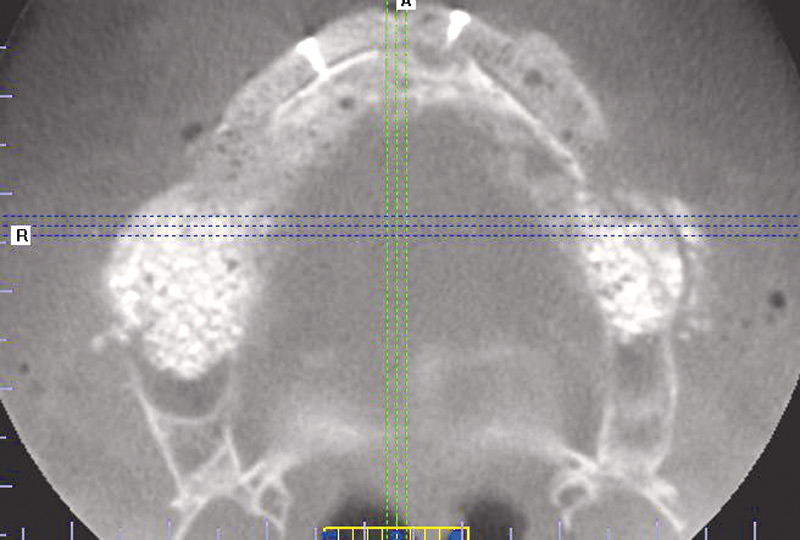

3/23 - Preoperative radiological situation – severely atrophic maxilla

Full arch reconstruction of the maxilla with maxgraft® bonebuilder - Dr. M. Erbshäuser